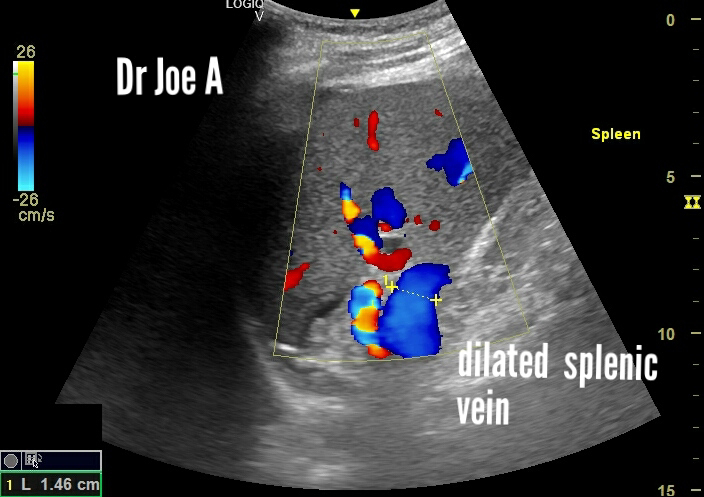

* Splenic vein:15 mm, exceeding normal diameter and further supporting portal hypertension.

* Splenic vein: Decreased in diameter, reflecting reduced portal congestion.

* Reduced size of spleen and splenic vein points to improved portal blood flow.